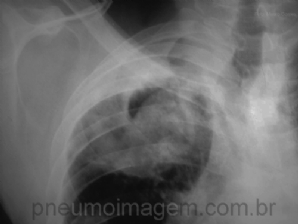

CASO CLÍNICO #13

Paciente com histórico de tuberculose apresenta-se com hemoptise e a seguinte imagem radiológica. Qual o diagnóstico mais provável? Deixe os seus comentários abaixo. ***** Patient with previous tuberculosis presents with hemoptysis and the following radi...